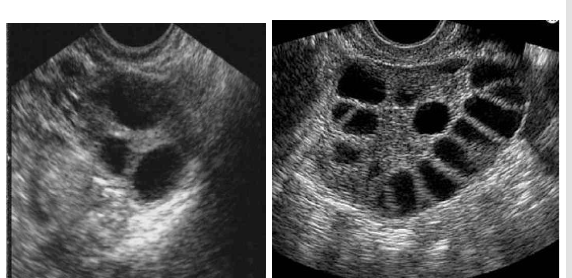

Explain the difference between normal ovary and PCOS?

What are the gross characteristics of the polycystic ovaries?

Bilateral enlarged ovaries with a smooth and thickened capsule

On cut section, multiple follicular cysts surrounded by abundant ovarian stroma are found throughout the cortex of the ovary

What is the ovarian morphology?

Classically, those with PCOS have enlarged ovaries with numerous peripheral small antral follicles and increased central stroma